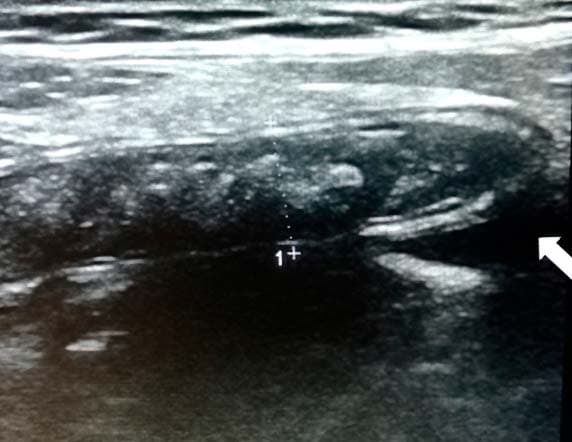

Рисунок 9. Картина УЗИ при гангренозном аппендиците.Из протокола УЗИ: «В правой подвздошной области визуализируется слепо заканчивающийся, не перистальтирующий участок кишки 10 мм в диаметре, болезненный при компрессии датчиком; в просвете жидкость и каловые камни» (см. рис. 9).

Из протокола операции: «Аппендикс резко утолщен, напряжен, грязно-серого цвета, покрыт фибрином». Диагноз после операции: гангренозный аппендицит (см. рис. 10).

Рисунок 10. Хирургически удаленный аппендикс при гангренозном аппендиците.Воспаленная жировая ткань (мезентериальный жир или большой сальник), окружающая воспаленный аппендикс, более эхогенная, чем в норме. Это делает аппендикс более заметным и облегчает его поиск за счет естественного контрастирования (см. рис. 11, 12).